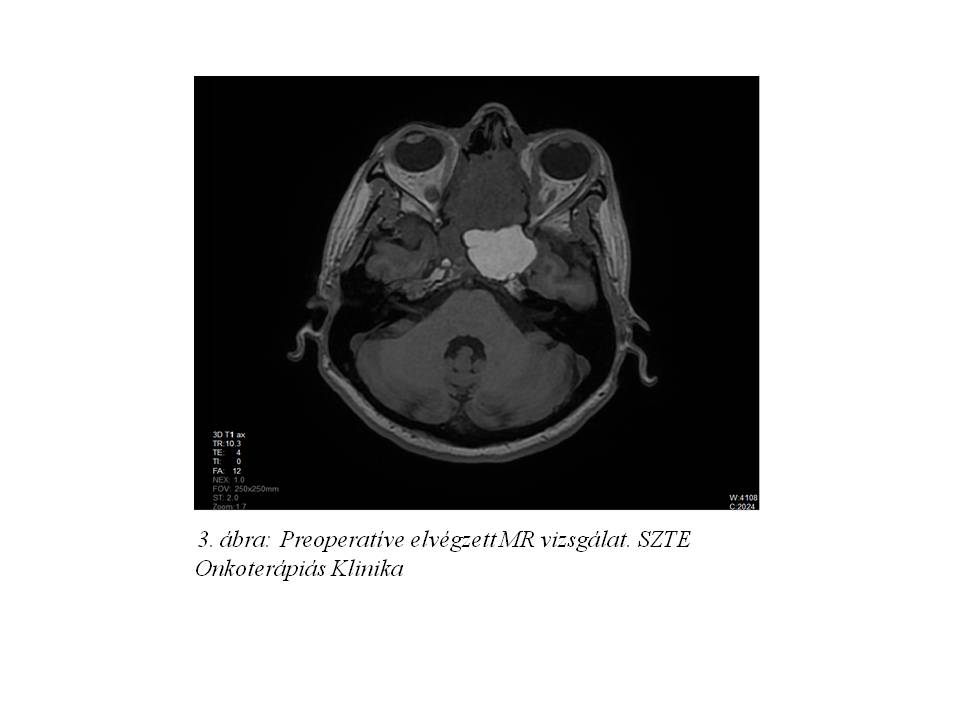

Panaszai kapcsán fül-orr-gégészetei szakvizsgálat, majd CT és MR vizsgálat történt. A felvételeken a lamina cribrosából kiinduló és mind a nyálkahártyát, mind a durát elemelő, az orr- és a koponyaüregbe egyaránt beterjedő terime ábrázolódott, amely a sinus sphenoidalist lezárta, ezzel jelentős folyadékgyülemet is okozva. (1. ábra, 2. ábra, 3. ábra). Fizikális vizsgálattal a beteg neurológiai statusban durva eltérés nem igazolódott.